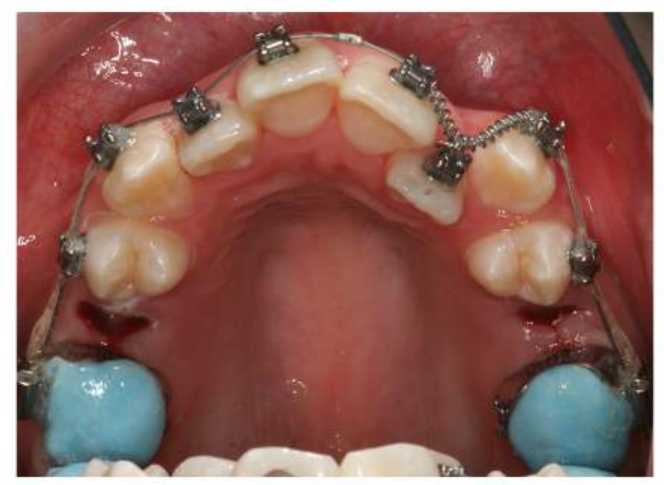

This pt has crowding, a centreline shift and a ant x-bite

What are the blue blocks on the upper 6’s here for?

There are blue blocks on the upper 6’s to disclude the bite allowing for the correction of the anterior crossbite.